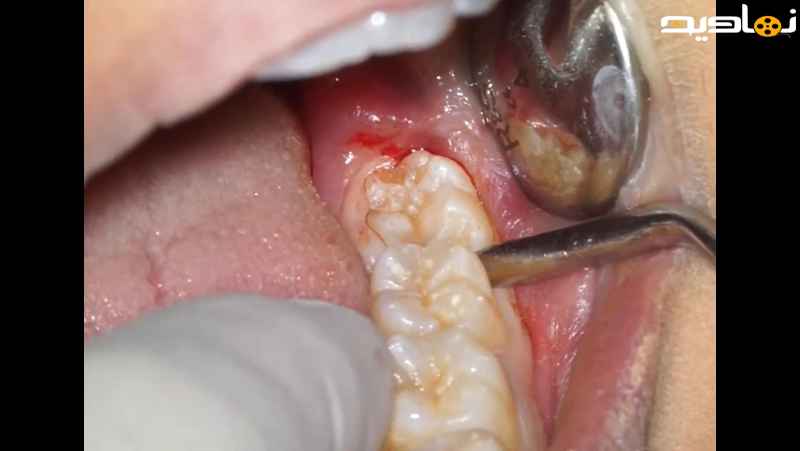

عمل جراحی برش دندان عقل به فک پایین

عمل جراحی برش دندان عقل به فک پایین یک روش جراحی است که برای از بین بردن دندان عقل که به صورت نامناسب رشد کرده استفاده می شود. در این روش، دندان عقل از داخل لثه بریده شده و از جای خود جدا شده و سپس خارج می شود. این عمل جراحی معمولا توسط یک جراح دهان و فک ها انجام می شود و ممکن است نیاز به تحت بیهوشی قرار گیرد. این روش برای پیشگیری از احتمال بروز عفونت، تراکم دندان ها و درد ناشی از دندان عقل نامناسب مفید است.